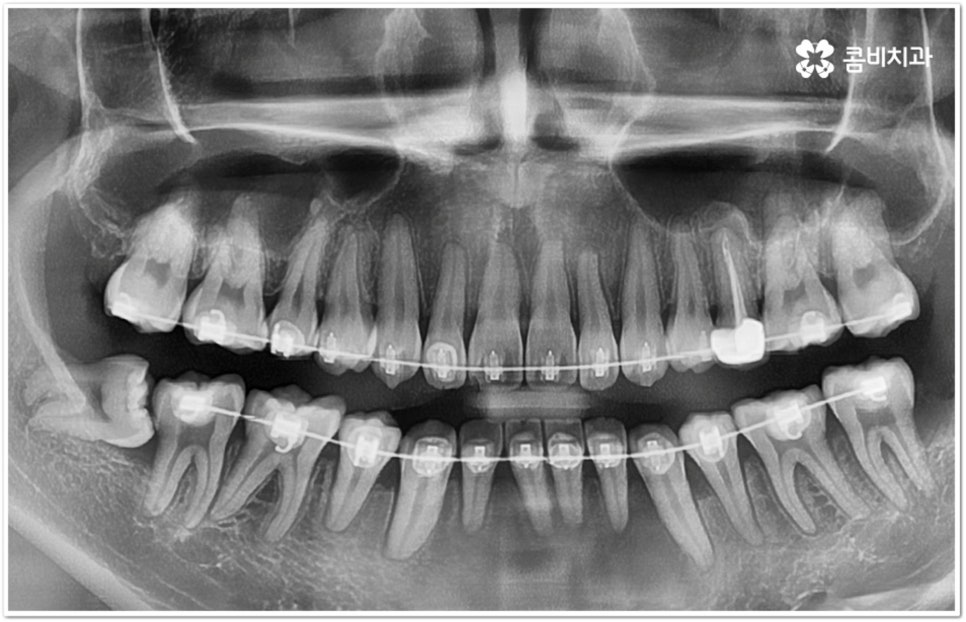

만약 똑바로 자라나고 관리가 용이하며 마주보는 대합치 역시 정상적으로 맹출되었다면 사랑니를 꼭 발치할 필요는 없을 거예요. 그러나 보통 사랑니는 사람의 치아 중에 가장 마지막에 나오는 치아라서 이미 구강 내 공간이 비좁은 상태이기 때문에 비스듬하게 자리를 잡고 일부분만 맹출이 되는 경우가 많이 있어요. 보통 머리가 앞쪽으로 기울어진 근심위로 자리잡는 케이스가 가장 많으며 그 밖에도 치아 머리가 뒤쪽으로 기울어져 있거나 혀쪽, 볼쪽으로 누운 케이스, 아예 옆으로 완전히 누운 케이스 등도 발견되고 있는데요.

잇몸에 반쯤 덮힌 채로 삐뚤게 나온 사랑니는 칫솔질을 제대로 하기 어렵고 위생 관리가 잘 되지 않아 주변 잇몸에 염증이 생기기 쉬우며 어금니까지 충치가 번질 위험이 높아지게 되어 구강 건강 관리 및 예방 차원에서 발치 처치를 해주실 필요가 있어요. 발치 난이도는 사랑니의 경사 각도와 방향 및 치아 뿌리의 길이와 개수, 사랑니 뒤쪽 턱 뼈의 각도 및 형태, 하치조 신경 또는 상악동까지의 거리 등에 따라서 달라질 수 있습니다.

이때 아래사랑니발치 의 경우 아래턱 부근을 지나가는 큰 신경인 하치조 신경을 건드리지 않고 조심스럽게 사랑니만 제거해야 하기 때문에 3D-CT 등 정밀 검진 기계를 통해 사랑니의 매복 위치, 깊이, 각도 등의 상태와 신경까지의 거리 등을 먼저 꼼꼼하게 파악한 후에 발치를 해 줄 필요가 있는데요. 만약 완전히 매복되어 있다면 사랑니 주변에 함치성 낭종이 발생할 수도 있는데 이로 인해 주변 치조골이 파괴되고 어금니 쪽으로 병변이 확산되면 결국 치아를 상실하게 되거나 턱뼈가 약해져서 작은 충격에도 부러지는 현상이 발생할 가능성도 있으므로 될 수 있는대로 치료 시기를 놓치지 않는 것이 중요한 포인트라고 할 수 있어요.

아래사랑니발치 와 다르게 윗 사랑니 발치 시에는 상악동까지의 거리가 너무 짧을 경우 천공 및 감염의 위험이 있으니 이에 대해서 3D CT 를 통해 꼼꼼하게 확인하고 환자분들의 상황에 맞는 치료를 진행할 필요가 있어요. 예를 들어 사랑니로 인한 문제가 크지 않은 경우 그대로 두고 지켜볼 수도 있고 다른 치료를 하는 중에, 즉 교정이나 임플란트 등을 진행하는 과정에서 발치가 꼭 필요한 경우라면 상악동 거상술, 뼈이식 등의 치료를 선행하여 무리하지 않게 뽑아주는 것이 좋을 거예요.

교정 치료를 하기 전에 사랑니를 먼저 발치해야 하는지 문의주시는 분들이 있는데 이 역시 검진 후에 환자분들의 상황에 맞게 결정하는 것이 좋기 때문에 교정과 사랑니 발치에 두루 임상 경험이 풍부하신 의료진을 선택하시면 치과를 옮겨다니는 번거로움 없이 보다 편안하게 적기에 필요한 치료를 받으실 수 있습니다. 또한 처음부터 끝까지 책임지고 철저하게 케어해 주는 치과의 도움을 받으시면 업무 때문에 많이 바쁘신 직장인 분들의 경우 시간을 단축시킬 수 있어 좋을 뿐 아니라 환자분들이 느끼실 수 있는 여러가지 심적인 부담도 덜 수 있을 거예요.